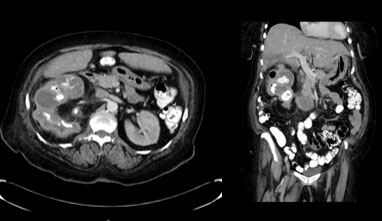

More recently, the patient presented with acute onset fevers and right flank pain. Computed tomography (CT) abdomen and pelvis showed xanthogranulomatous pyelonephritis as well as a perinephric abscess. The patient underwent percutaneous drainage of the abscess and placement of a nephrostomy. The patient underwent antegrade nephrostogram which demonstrated contrast in the small bowel and reno-duodenal fistula (Figure 2 and Figure 3). Initially, the patient was treated conservatively with intravenous antibiotics. Nuclear scan of the kidney showed it to be a non-functional kidney as a result of the infection.

Figure 2: CT scan showing xanthogranulomatous pyelonephritis (XGP) kidney.

Share Image: